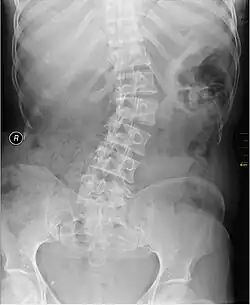

X-ray of individual with scoliosis

Scoliosis has been known to cause unilateral iliocostal friction syndrome.[5] It is a condition in which the lateral curvature of the spine is measured to be more than 10 degrees. Scoliosis is typically categorized into congenital, neuromuscular, idiopathic, degenerative, and pathologic forms.[7] The decreased distance between the ribcage and the iliac crest can come in contact depending on the severity of the scoliosis curve.[8] There has also been reported instances where individuals experience iliocostal friction syndrome due to an abnormally long twelfth rib. This can be presented both bilaterally or unilaterally, depending on the individual.[3][8]